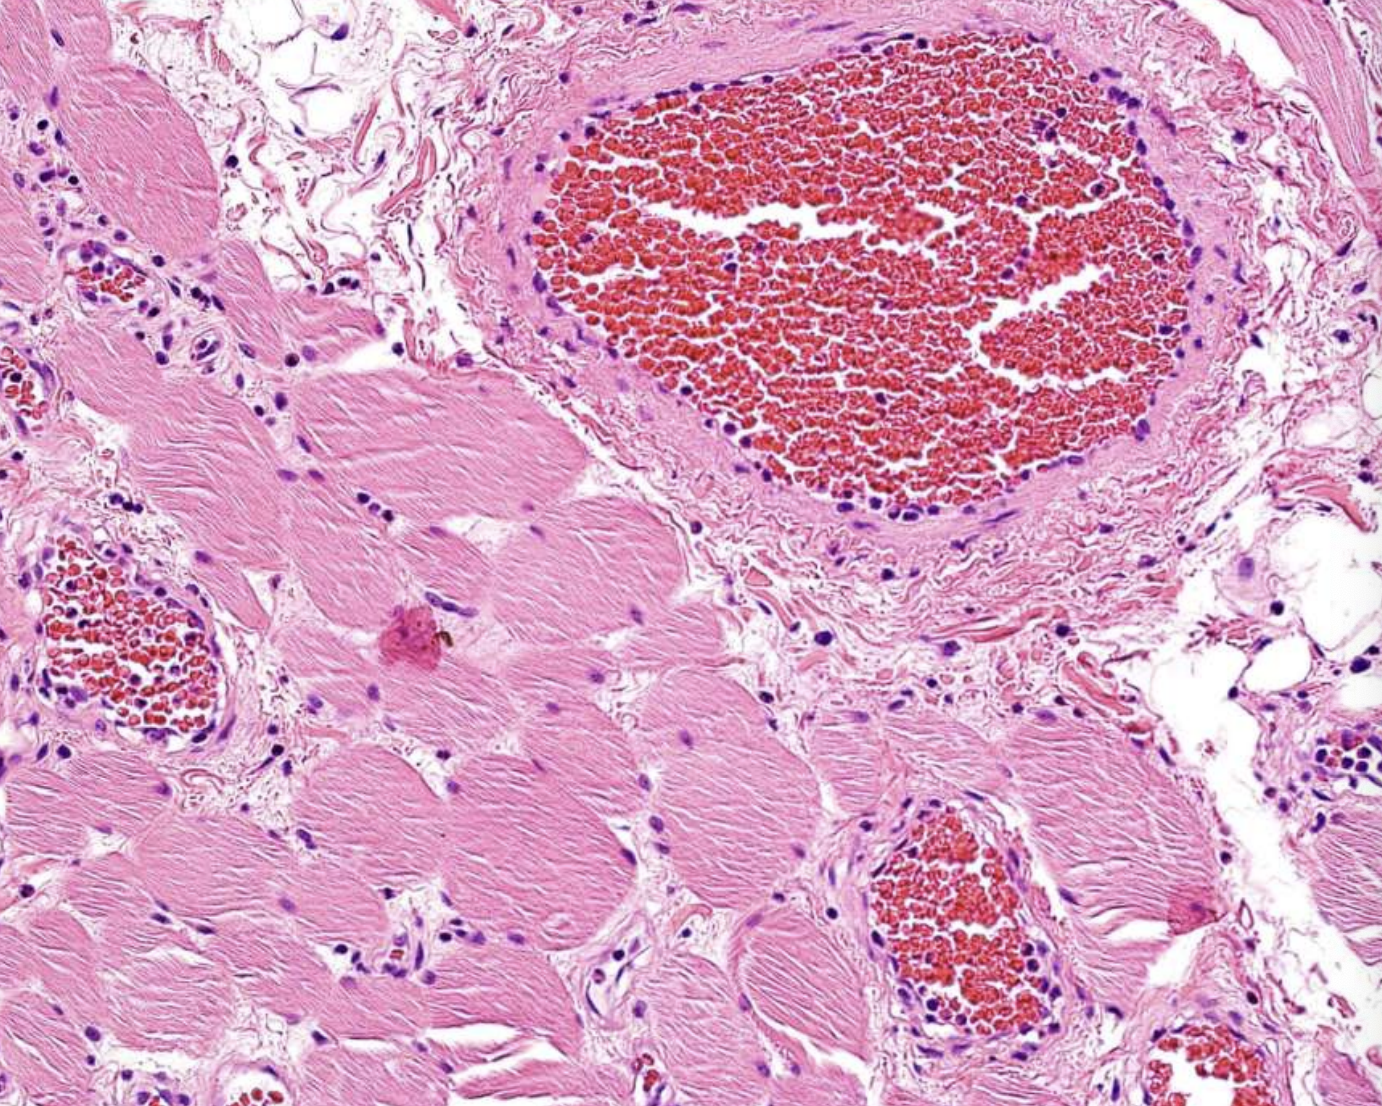

what are histopathologic features of Central Vascular Malformation?

Proliferation of capillaries and endothelial cells containing abundant blood